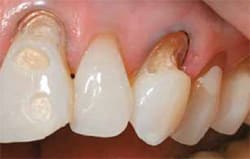

- Severe erosion of the anterior dentition was present upon clinical examination, extending past the enamel into the dentin.

| Note extent of patient’s cavities.(View Figure) | Note extent of patient’s cavities.(View Figure) | ||||||